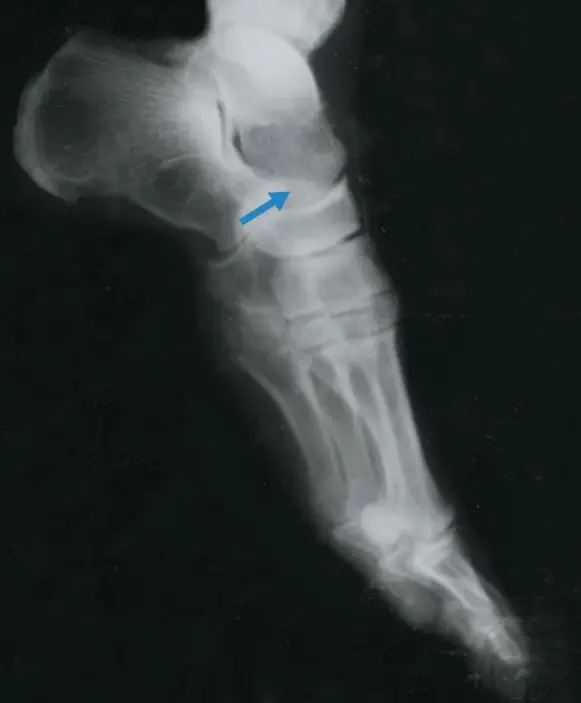

圖中箭頭所指是那一塊骨頭?

本題提供的是一張處於極度蹠屈(plantar flexion)狀態的足部側位X光影像。

- 跟骨(Calcaneus):影像左上方體積最大、向後方突出的骨骼,是構成足跟的基礎。

- 距骨(Talus):位於跟骨的上方與前方。影像最頂端可見其圓頂狀的結構,稱為距骨滑車(talar dome)。藍色箭頭明確指向這塊骨頭的前段(距骨頸與距骨頭的位置)。

- 舟狀骨(Navicular):位於箭頭尖端右側,與距骨頭相連接,兩者形成距舟關節(talonavicular joint)。

- 骰骨(Cuboid):位於跟骨的遠端(影像中相對下方的位置),與跟骨形成跟骰關節(calcaneocuboid joint)。

- 蹠骨(Metatarsals):位於影像最右下方的數根長骨。